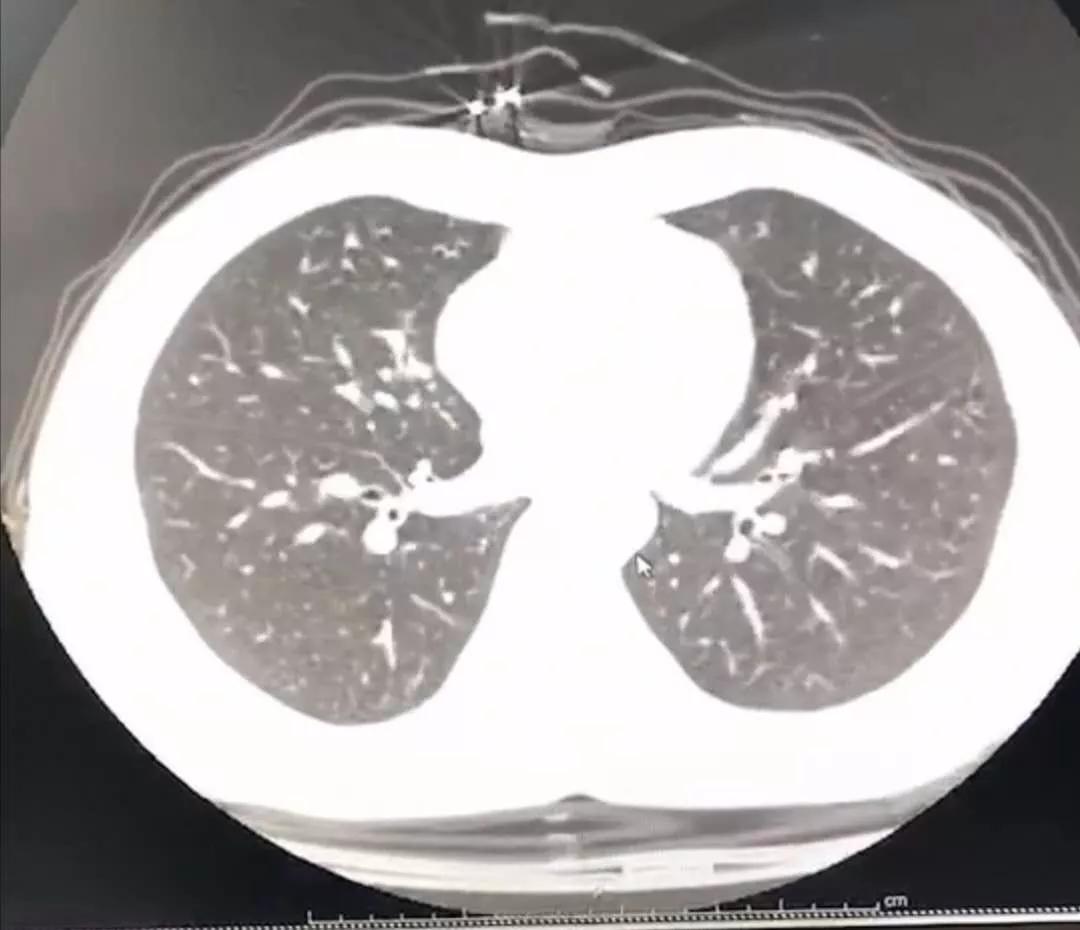

于是拖着沉重的步伐,我又从家里出发去医院做胸部CT。幸运的是肺部还没有出现病毒性肺炎的特征性影像学表现,说明就算是新型冠状病毒感染,目前还属于轻型,没有实质性地累及肺组织。